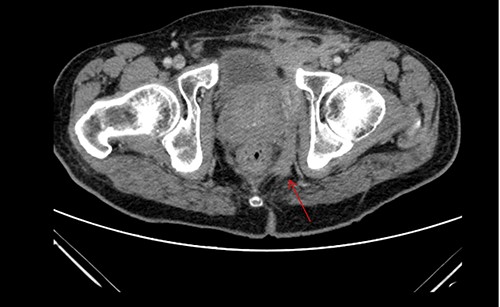

A 61-year-old diabetic patient was admitted from emergency department with septic signs; fever of 39°C, white blood cell count of 20.000/μl, C-reactive protein levels of 156 mg/l and blood glucose levels of 280 mg/dl. For the past 10 days, the patient has noted malodorous anorectal pus discharge, as well as anorectal and suprapubic pain. During macroscopic examination of the perineum, a left-sided abscess in the ischiorectal fossa was identified, with an opening lateral to the sphincteric anal system draining pus. Subsequent digital rectal examination of the anorectal canal could not be completed due to pain, but the initial effort revealed large amounts of pus discharged from anorectal canal. CT and MRI demonstrated an abscess situated in the left ischiorectal fossa and a large supralevator abscess extending cephalad in the extraperitoneal space with a long fistulous tract containing liquid (pus) and gas bubbles, up to the suprapubic area, where erythema with an undulating pus collection below the skin was noted; laterally the pus collection extended up to the left ilio-femoral vessel canal. CT (Fig. 1) and MRI (Fig. 2) were conclusive for the above entity, aptly demonstrating the presence of the two abscess cavities. Proctoscopy under general anesthesia revealed a protruding extra-rectal mass in the left lateral and inferior segment of the rectal ampulla. Finger pressure at this point was accompanied with pus exit from the posterior dentate line of the anal canal at 6 o’clock, through an opening of 1–2 mm in size. Surgery was addressed in three main locations of the pus collection with goal to drain completely the pus; the abscess of the left ischiorectal fossa was drained with enlargement of the external opening of fistula; after curettage, debridement and washing of abscess cavity, a probe was used to detect the internal opening exactly at the posterior dentate line at 6 o’clock. The fistula was characterized as full trans-sphincteric with an extra-sphincteric component in the ischiorectal fossa leading up to the skin. A non-cutting vessel loop drainage seton was then placed. The supralevator abscess was then easily drained from the opening in the posterior dentate line by finger pressure in the left rectal ampulla. A probe following the route of the internal opening upwards to supralevator space led to pus evacuation, allowing this space to be thoroughly washed with water saline solution, using a syringe with a vein catheter. Finally, the suprapubic area was drained with a small stab incision, followed by washing with normal saline. There was a prompt recovery postoperatively, tight control of blood glucose levels, whereas a CT performed 7 days postoperatively (Fig. 3), demonstrated an empty supralevator space with a fistulous tract still present, albeit with significant regression of inflammatory changes.

Postoperative CT of the lower pelvis, demonstrating a collapsed left supralevator space and superiorly expanding fistulous tract.